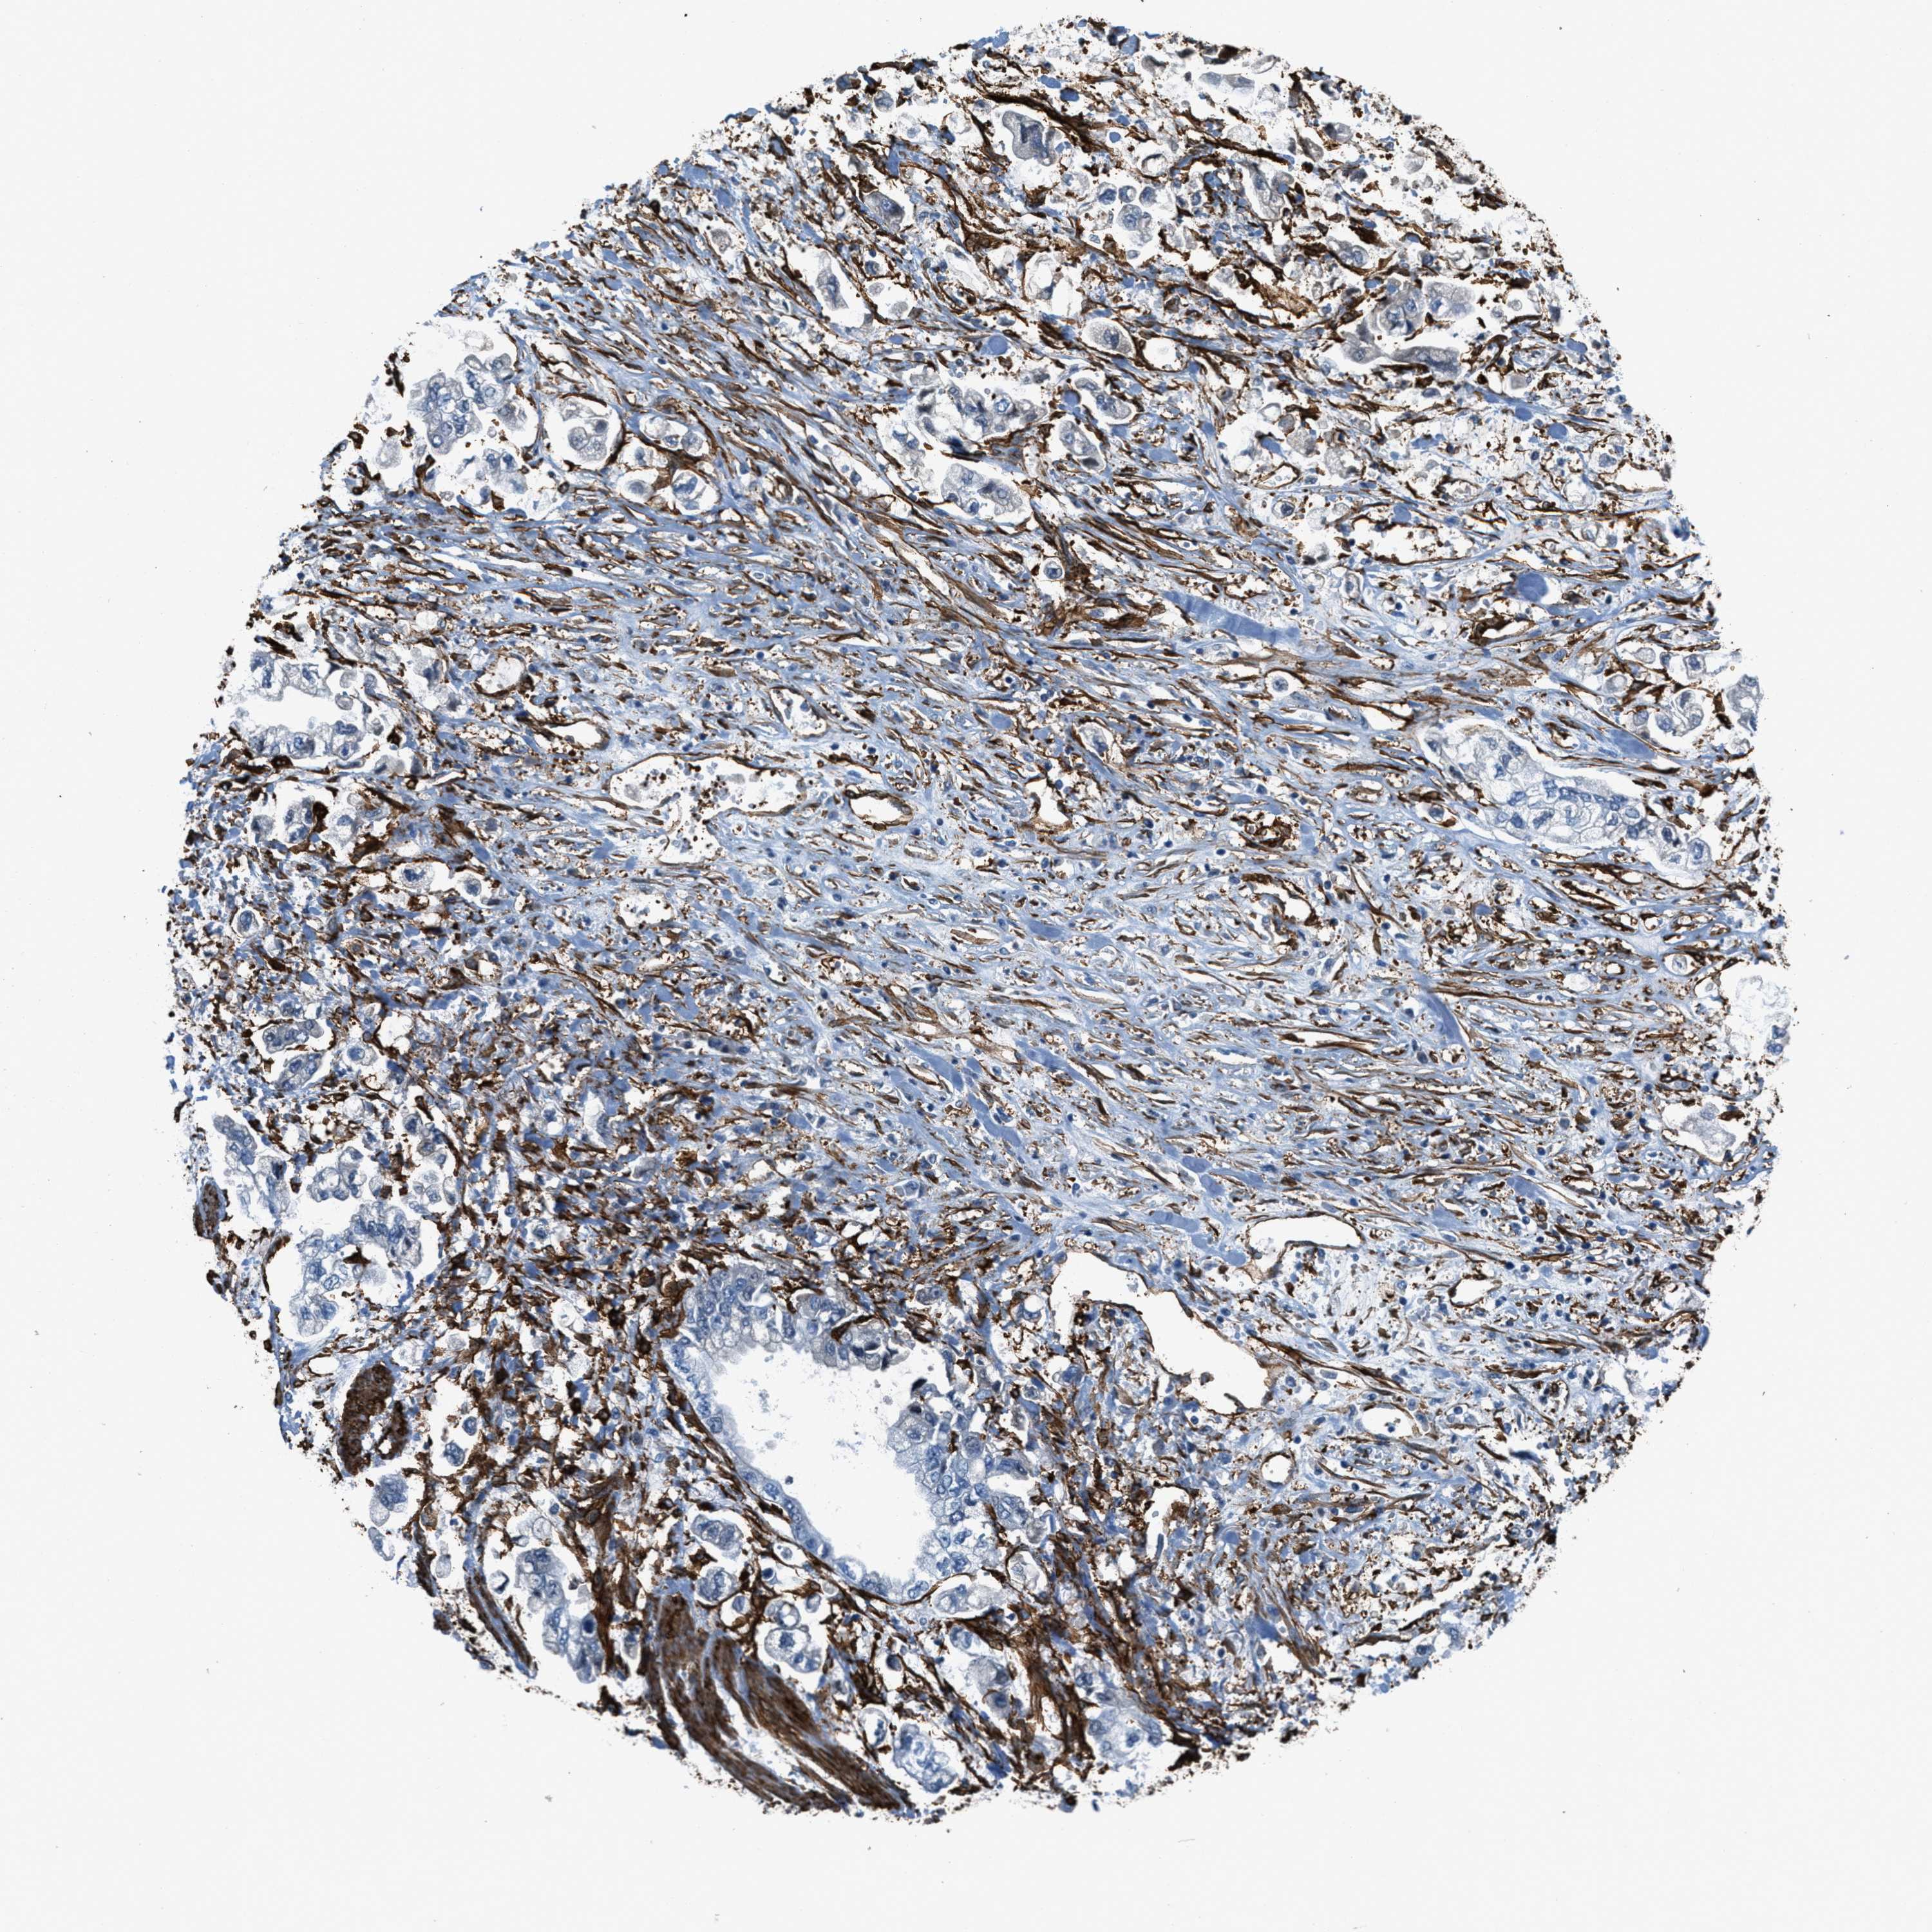

STOMACH CANCER - Protein expressioni

A mouse-over function shows sample information and annotation data. Click on an image to view it in a full screen mode. Samples can be filtered based on level of antibody staining by selecting one or several of the following categories: high, medium, low and not detected. The assay and annotation is described here.

Note that samples used for immunohistochemistry by the Human Protein Atlas do not correspond to samples in the TCGA dataset.

Antibody stainingi

Antibody staining in the annotated cell types in the current human tissue is reported as not detected, low, medium, or high, based on conventional immunohistochemistry profiling in selected tissues. This score is based on the combination of the staining intensity and fraction of stained cells.

Each image is clickable and will lead to virtual microscopy that enables deeper exploration of all samples and also displays staining intensity scores, fraction scores and subcellular localization as well as patient and tissue information for each sample.

Antibody HPA008066

Antibody HPA017330

Antibody CAB000006

Staining

High

Medium

Low

Not detected

Intensity

Strong

Moderate

Weak

Negative

Quantity

>75%

75%-25%

<25%

None

Location

Nuclear

Cytoplasmic/membranous

Cytoplasmic/membranous,nuclear

Adenocarcinoma, NOS